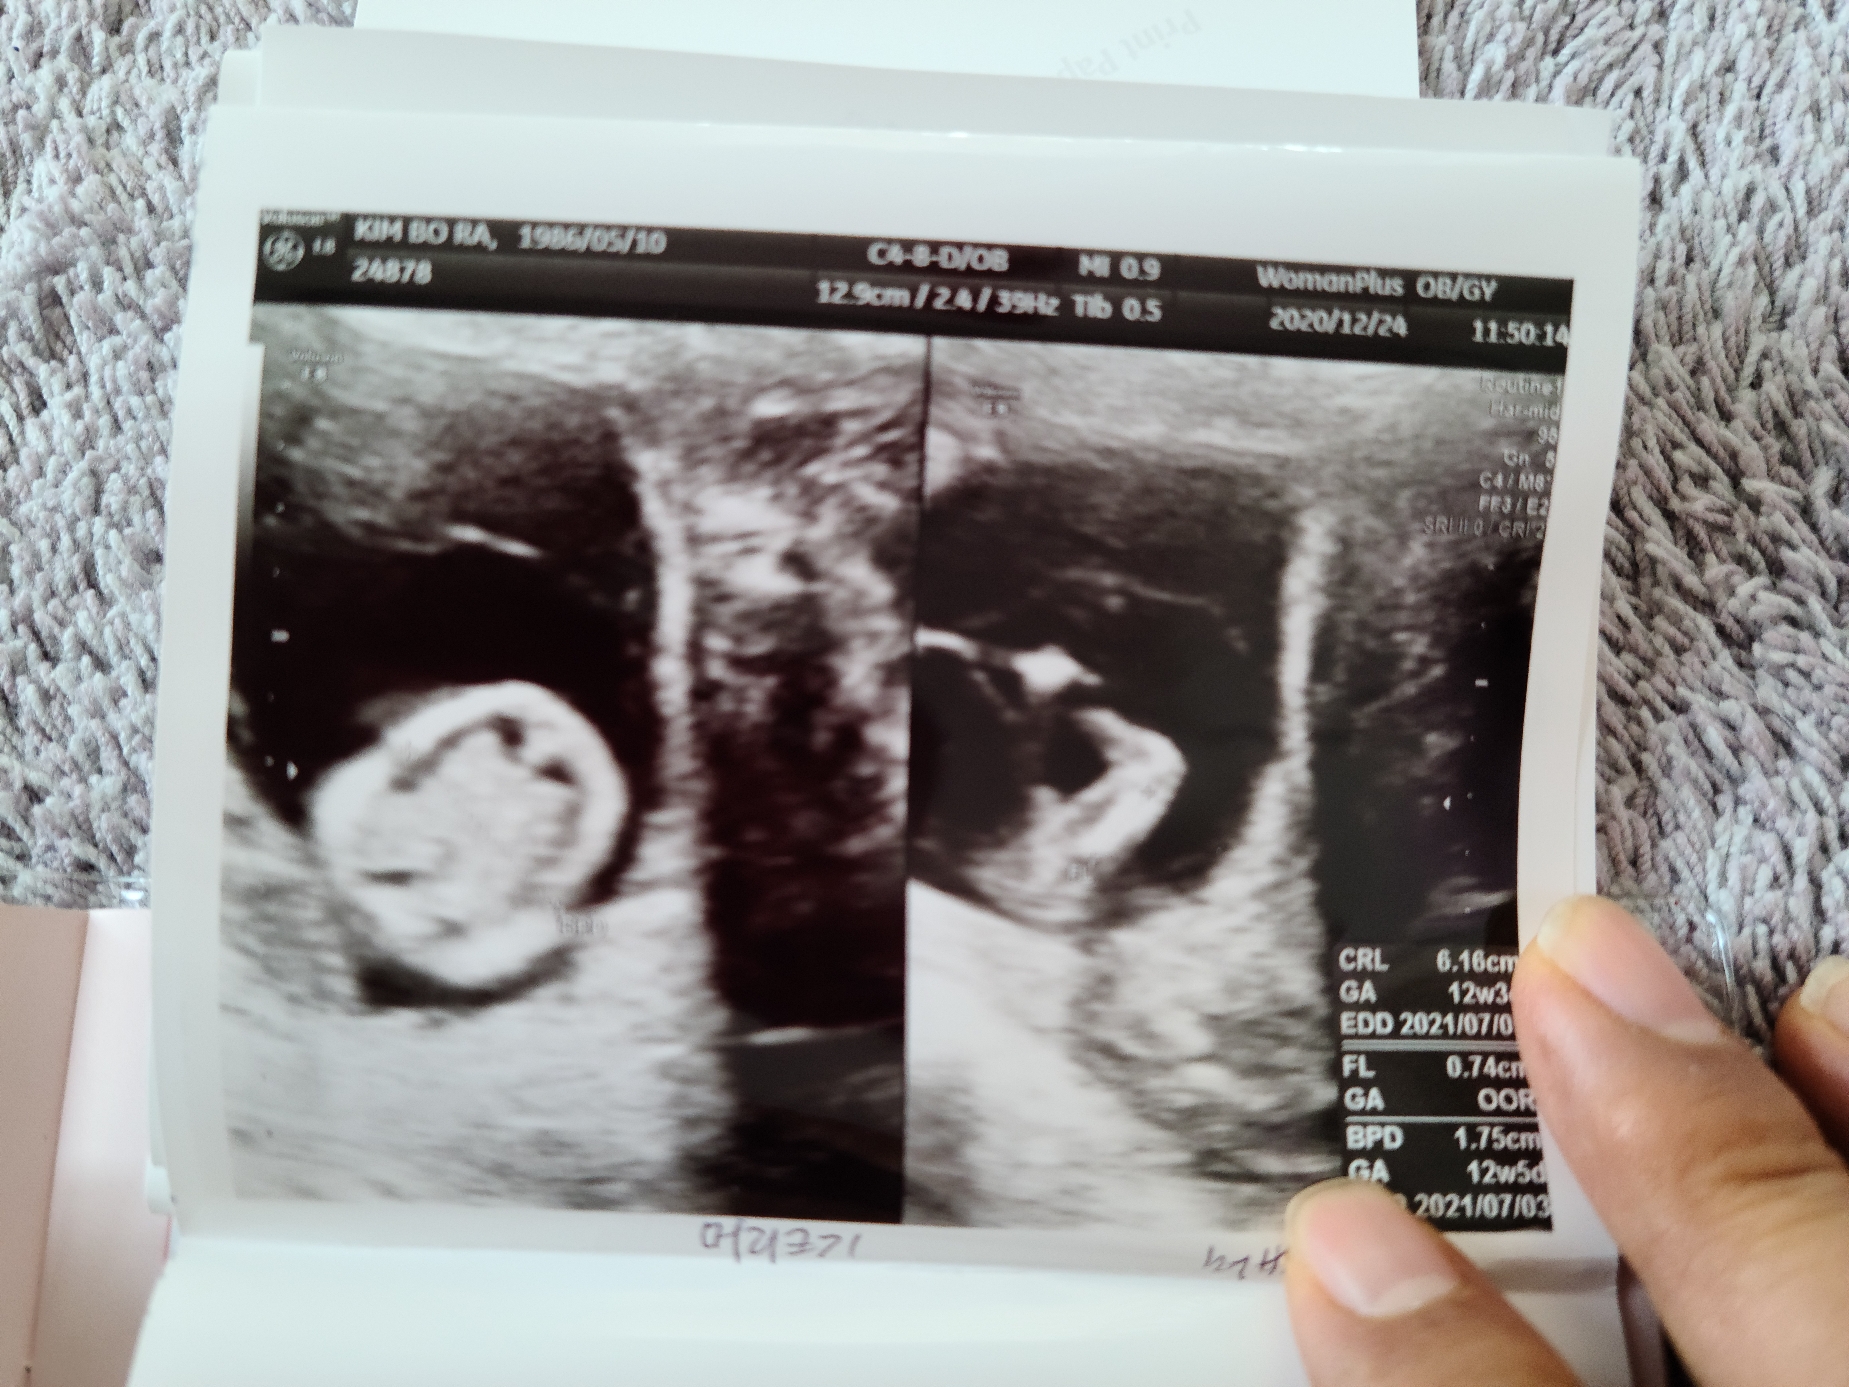

불안한 마음에 병원에 가서 검사한 결과 다행히 아무런 이상없이 건강하게 자라고 있음을 확인했어.

엄마 뱃속에서 뛰고 있는 무탈이 심장을 보며 아빠는 고마움과 기쁘이 남쳐 눈물이 고였다.